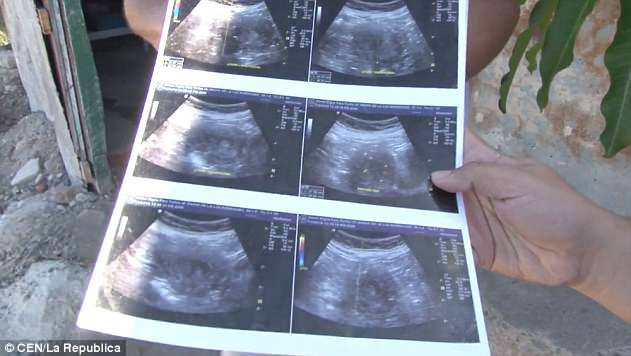

70歲的墨西哥婦人Maria de la Luz聲稱自己現懷有6個月身孕,並展示超聲波掃描照片,表示她確實懷有一名女嬰。倘若屬實,Maria de la Luz將成為全世界最年長的孕婦,比現有紀錄保持者年長4年。

Maria de la Luz說:「當時我嘔吐、頭暈和腳痛,在私人診所和公立醫院前後做了10次左右的超聲波掃描,醫生亦不敢相信我懷孕。」